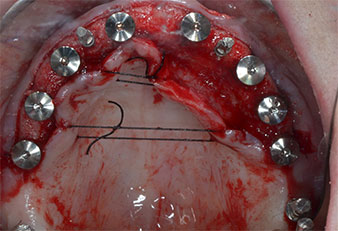

Wegen des relativ harten Knochens (D2) an den Positionen 11 und 21 wurden die 10 mm langen Implantatlager in diesem Bereich abschließend mit einem 4-mm-Spiralbohrer, dem chirurgischen Winkelstück WS-75 L von W&H und dem W&H Implantmed Implantologiemotor in Verbindung mit dem optionalen W&H Osstell ISQ module präpariert. Im Gegensatz dazu wurde der weiche Knochen der Implantatlager im Seitenzahnbereich mit dem Piezomed I3P auf den abschließenden Durchmesser von 3 mm erweitert. Die Implantate wurden dann transgingival eingesetzt, die Einheildauer betrug drei Monate (Abb. 6-10). Die vorhandene Prothese wurde auf vier provisorischen Implantaten abgestützt (Abb. 8).